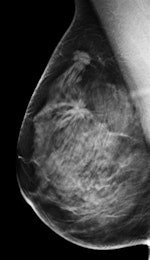

The Italian study was published online on 14 September in European Radiology. Lead author Dr. Gisella Gennaro, a medical physicist from the Veneto Institute of Oncology in Padua, and colleagues compared the clinical performance of standard two-view digital mammography with the combination of one-view tomosynthesis (mediolateral oblique) and one-view mammography (craniocaudal). A multiple-reader, multiple-case receiver operating characteristics (ROC) experiment was performed, and clinical performance was reported in terms of area under the ROC curve (AUC), sensitivity, and specificity.

In addition, using DBT with a single complementary mammography view could allay radiologists' fears about the detection of subtle microcalcifications -- current studies show DBT's sensitivity for detecting calcifications is lower than mammography's. The combined technique proposed in Gennaro's study could aid calcification detection and help train radiologists to recognize and properly rate calcifications on DBT images.

"It is possible that a benign lesion was not seen by mammography and that the breast was therefore considered normal, but the benign lesion appeared on DBT because of the better separation of superimposed breast tissue when viewing individual tomographic planes," they stated. "Another possible reason is that, despite readers knowing that DBT reduces superimposed anatomical noise, overlapping tissues observed in the craniocaudal mammography were not disregarded because of readers' greater confidence with the established technique."